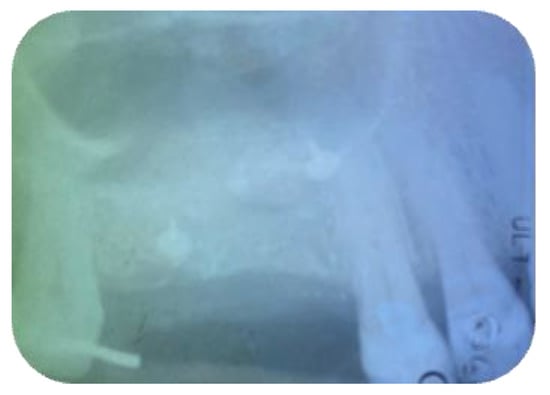

Long-Term Outcomes of Implants Placed in Maxillary Sinus Floor Augmentation with Porous Fluorohydroxyapatite (Algipore® FRIOS®) in Comparison with Anorganic Bovine Bone (Bio-Oss®) and Platelet Rich Plasma (PRP): A Retrospective Study

2. Materials and Methods

3. Results